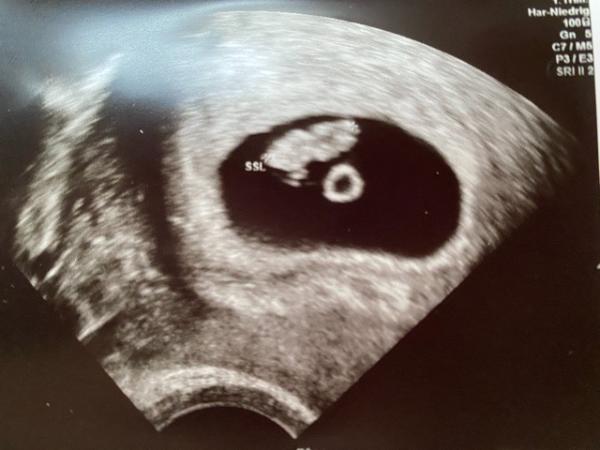

Hallo zusammen, heute war ich bei meinem ersten Ultraschall. Das Baby ist 1,2 cm und 7+1-3. kräftiges Herzschlag habe ich sehen können. Die Ärztin war zufrieden, alles wie es sein soll. Für mein Geschmack war sie aber zu schnell und nicht konkret genug. Aber, was will man mehr??? Hauptsache dem Krümelchen geht es gut.

Bild zu Ultraschall 7+1-3 - Forum für Juni - Mamis